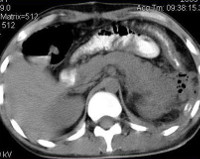

Что такое флегмоны забрюшинного пространства - фото презентация